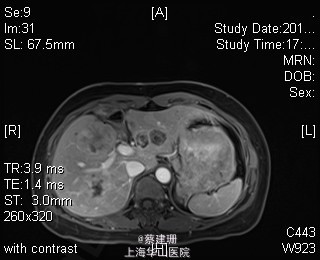

主诉:平滑肌肉瘤、肝转移癌术后,发现肝多发转移2月余。 现病史:患者3年前外院检查发现后腹膜肿瘤,外院行后腹膜肿瘤切除术后,术后病理为:平滑肌肉瘤,2013年12发现肝左叶转移癌,外院行肝左叶肿瘤切除术,术后病理为:梭行平滑肌肉瘤。2月余前患者复查发现肝脏多发转移,2015-4月肝脏MRI:肝脏多发转移。现患者无恶心、呕吐,无呕血、黑便,无皮肤巩膜黄染,无剧烈腹痛发作。现为进一步诊治收住入院。

查体:锁骨上淋巴结未扪及肿大;腹部平坦,可见陈旧性手术疤痕。未见肠型、胃型蠕动波,腹软,无压痛及反跳痛,无肌卫,肝脾肋下未及。Murphy’s 征(-),肝区叩击痛(-),肾区叩击痛(-);移动性浊音阴性。 辅查:2015-4月肝脏MRI:肝脏多发转移。

诊断 :1、多发肝转移癌 2、后腹膜平滑肌肉瘤术后 3、肝转移癌术后 处理:取右侧肋缘下切口,左侧延长,逐层切开进腹,探查腹腔:见上腹部粘连,仔细游离上腹部腹腔粘连,探查见无腹水,胃、肠、胰、脾及盆腔脏器未及异常,腹腔未见明显转移结节;肝脏无硬化。肝门淋巴结无肿大,门静脉主干无栓子。肿瘤多枚,最大两枚位于肝右叶VI段,肿瘤大小约7*6*5cm。V段肿瘤直径约5cm。左内叶肿瘤多枚,直径0.5-4cm,紧贴第一肝门。左外叶肿瘤多枚,直径1-3cm,肿块质韧,边界尚清,有包膜。术中诊断为转移性肝癌,决定行左半肝切除,肝右叶特殊肝段切除。